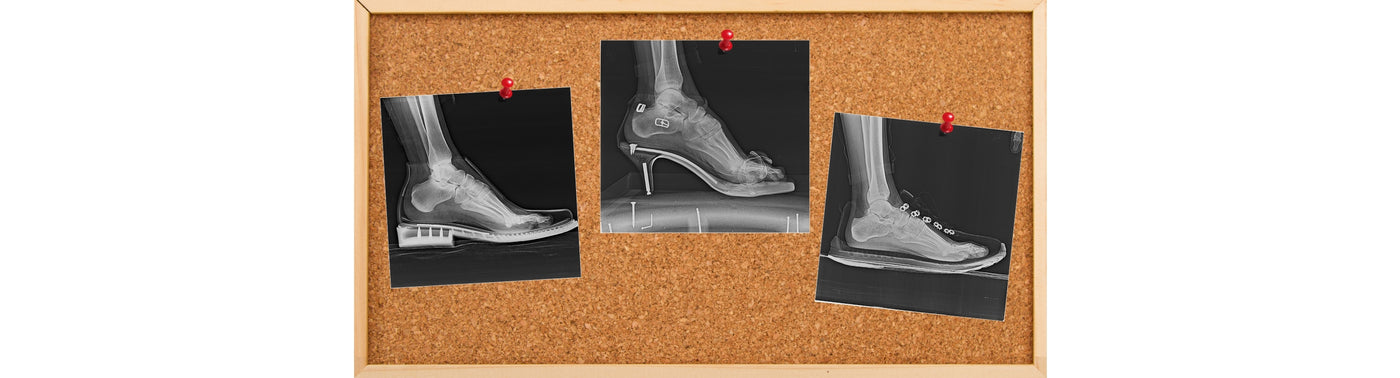

Tavallisten kenkien kapea varvastila, kantakorko ja paksut sekä jäykät pohjat luovat keinotekoisen ympäristön jaloillesi.

Ne rajoittavat jalkojesi luonnollista liikettä ja vähentävät aistimuksia maasta. Tämä keinotekoinen ympäristö vaikuttaa negatiivisesti koko kehoosi.